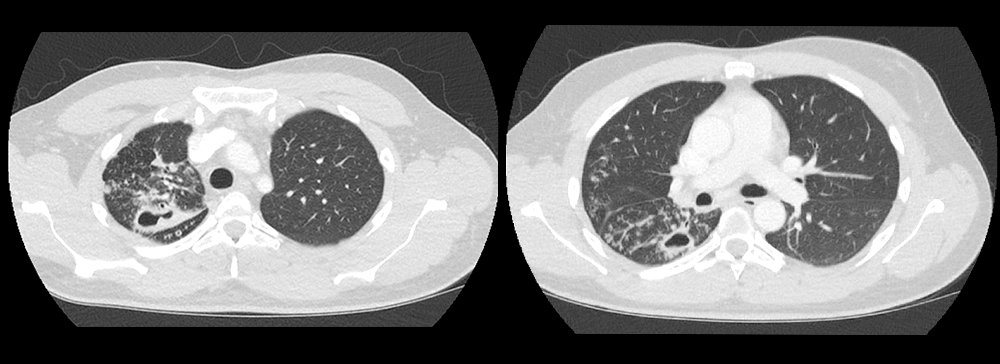

Chest CT

What best describes the findings on the Chest CT?

There is a cavitary lesion in the posterior portion of the right upper lobe. There is also endobronchial spread along nearby airways characterized by ill-defined fluffy air-space infiltrates, and sharply marginated linear branching opacities representing the tree in bud sign throughout the right lung. These findings are characteristic of tuberculosis infection.

View the full study if you'd like to like a look yourself